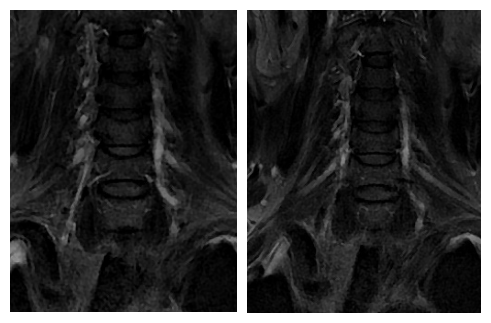

神经内科张桂莲教授带领的介入团队在影像科李晓会教授团队的鼎力支持下,反复查阅相关文献,尝试多种新型磁共振成像技术,最终历时4个小时,克服了肺内气体对磁共振成像质量的影响,通过特殊的MRI成像技术及体表定位技术,清晰显示出脑血管造影及高分辨核磁共振不能显示的闭塞的椎动脉开口,使之前无法完成的高难度手术变成可能。

最终,在患者入院第4天,张桂莲教授带领的介入团队选择局麻条件下为患者成功实施了神经介入领域的高难度手术—左侧无残端椎动脉长节段慢性闭塞再通术。因术前清晰的影像显影及准确的体外定位标记,左侧优势椎动脉顺利开通,手术耗时仅仅约90分钟。术中及术后患者配合良好,无任何不适,术后在介入准备室,张桂莲教授向患者女儿详细告知手术过程及患者目前状况,患者女儿喜极而泣,多次向介入团队表示感谢。